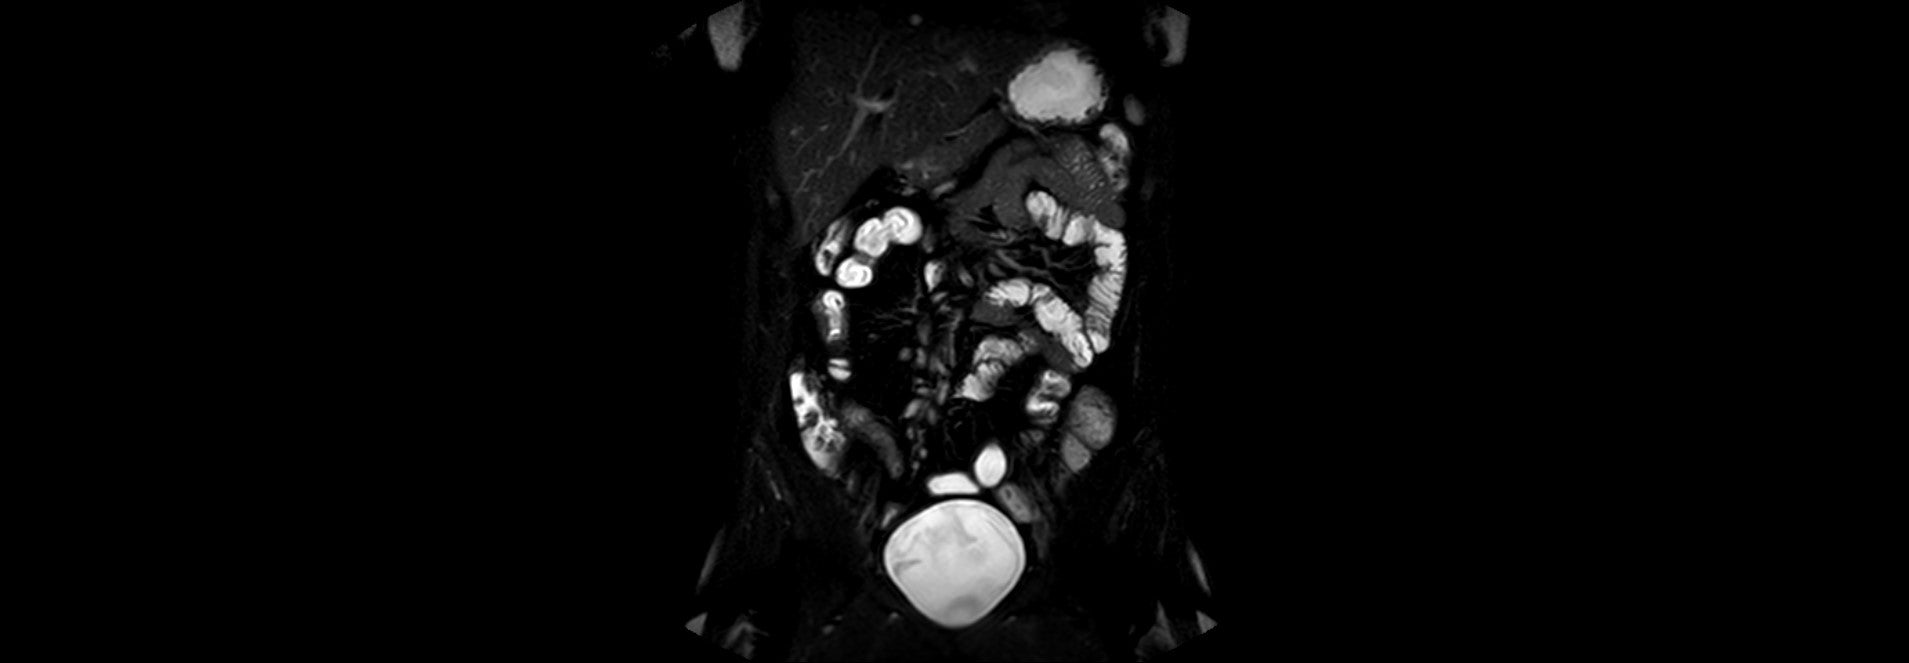

Zobrazovací metody:

MR enterografie ze dne 03.08.2023 - T2 vážený obraz s potlačením tuku

Klinika radiologie a nukleární medicíny FN Brno